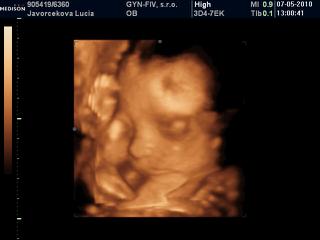

Lucy, nádherná je 😵

Bihan, dakujem 😵 ja som neobjektivna, pre mna je najkrajsia pod slnkom 😀

Lucy kraaaaaaaaaaaasna je 😵 😵 😵

A inak poloha je zadkom dole, hlavicka niekde v urovni pupka a nozky za hlavou a potom sa divim, ze mi kope hore 😀

Lucy, veď to je normálne, že pre teba bude vždy najkrajšia, ale má úplne objektívne nádherný malý nošte 😀

Lucy tiez si myslim, ze ma krasny maly nostek a to uuuuplne objektivne!